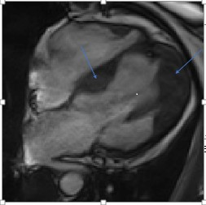

Fibrosis in the basal anteroseptal wall segment and in the apical lateral wall segment, with an estimated fibrosis mass of 17%